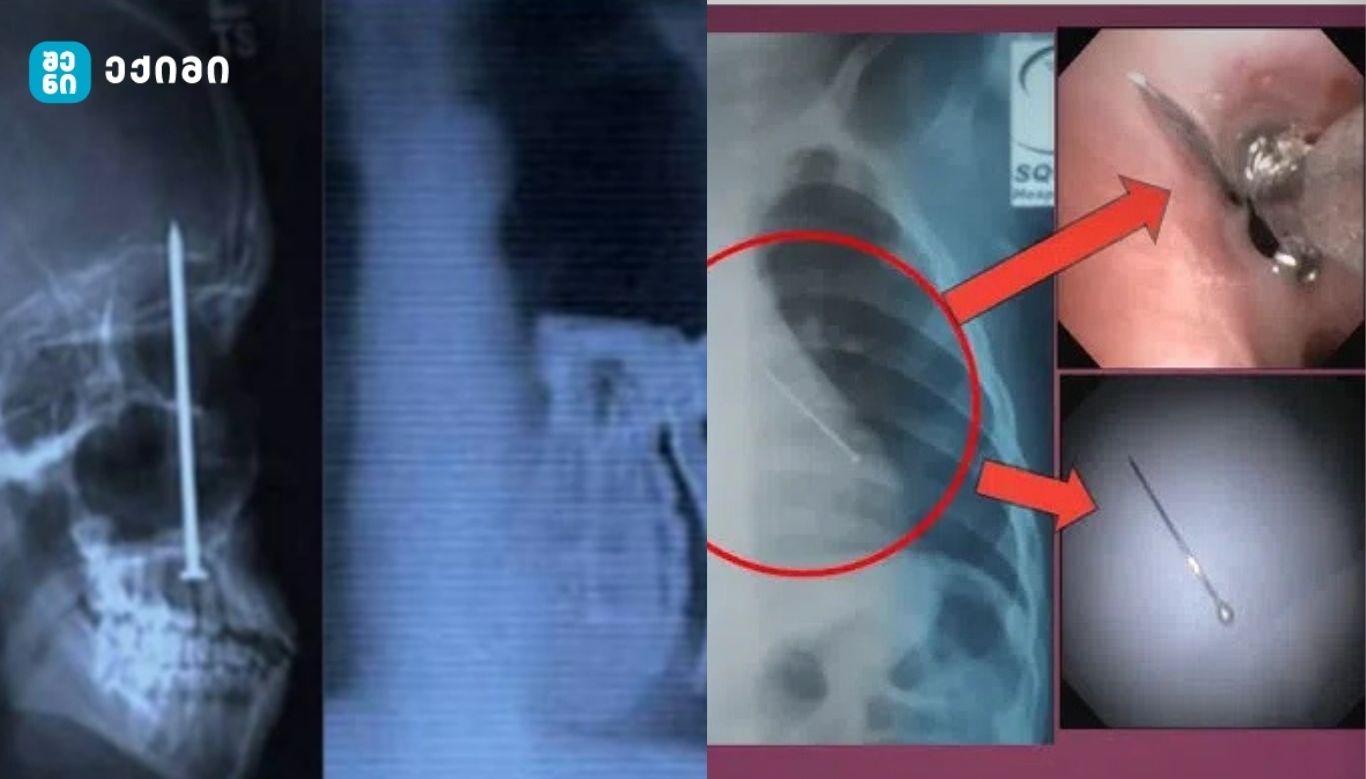

სამედიცინო დაწესებულებების მიერ გავრცელებული ფოტომასალა აჩვენებს სხვადასხვა საგნებს, რომლებიც პაციენტების ორგანიზმიდან იქნა ამოღებული, მათ შორის ყურსასმენები, სამკაულები და ლურსმნები. ერთ-ერთ ყველაზე მძიმე შემთხვევად აღინიშნა პაციენტი, რომელმაც რემონტის დროს კბილებს შორის მოქცეული ლურსმნები შემთხვევით გადაყლაპა. ექიმების განცხადებით, ასეთ შემთხვევებში პაციენტები ხშირად საჭიროებენ გადაუდებელ ენდოსკოპიურ ან ქირურგიულ ჩარევას და შემდგომ რეაბილიტაციას [1].

უცხო სხეულები, რომლებიც ხვდება კუჭ-ნაწლავის ტრაქტში, შეიძლება გამოიწვიოს ლორწოვანი გარსის ტრავმა, ანთება და მექანიკური ობსტრუქცია. ბასრი ან მყარი საგნები, როგორიცაა ლურსმნები და მეტალის ნაწილები, ზრდის პერფორაციის რისკს, რაც შეიძლება გადაიზარდოს პერიტონიტში და სიცოცხლისთვის საშიშ მდგომარეობებში [2].

კლინიკური კვლევები მიუთითებს, რომ დაახლოებით 80–90 პროცენტი გადაყლაპული საგნებისა ბუნებრივად გამოიყოფა, თუმცა 10–20 პროცენტში აუცილებელია ენდოსკოპიური ამოღება, ხოლო დაახლოებით ერთ პროცენტში — ქირურგიული ჩარევა [3]. რისკი განსაკუთრებით მაღალია იმ შემთხვევაში, თუ საგანი შეიცავს ბატარეებს, მაგნიტებს ან ბასრ კიდეებს.